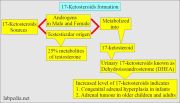

| 08:12, 28 בפברואר 2024 | Ketosteroids4.jpg (קובץ) |  |

154 קילו־בייטים | Motyk | 1 | |

| 08:08, 28 בפברואר 2024 | Ketosteroids3.jpg (קובץ) |  |

225 קילו־בייטים | Motyk | 1 | |

| 08:03, 28 בפברואר 2024 | Ketosteroids2.jpg (קובץ) |  |

268 קילו־בייטים | Motyk | 1 | |

| 06:49, 28 בפברואר 2024 | Ketosteroid 1.png (קובץ) |  |

7 קילו־בייטים | Motyk | 1 | |